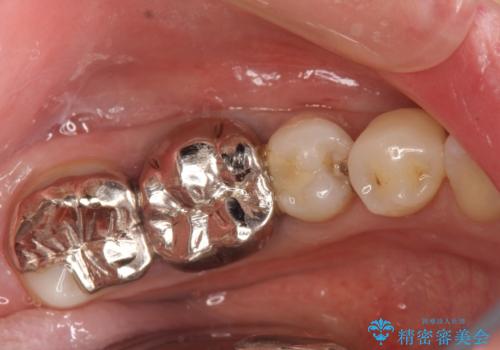

奥歯の被せ物のやり直し 精密根管治療

大きい虫歯 根管治療〜オールセラミッククラウン